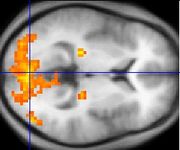

Neural

Studies using neuropsychological tests and brain imaging technologies such as fMRI and PET to examine functional differences in brain activity have shown that differences seem to most commonly occur in the frontal lobes, hippocampus, and temporal lobes. These differences have been linked to the neurocognitive deficits often associated with schizophrenia. The role of antipsychotic medication, which nearly all those studied had taken, in causing such abnormalities is unclear.